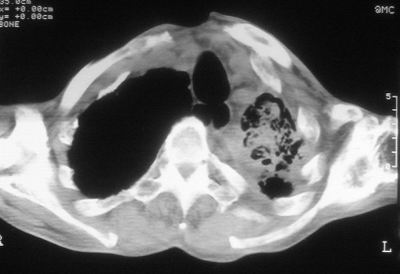

标题: CT11864:男,47岁,反复咳嗽、咯痰、咯血3年,请分析. [打印本页]

患者,男,47岁,反复咳嗽、咯痰、咯血3年,再发5天。痰培养未找到真菌、抗酸杆菌、癌细胞。

以下是引用xulianj在2008-2-25 21:01:00的发言:[br]左肺上叶结核伴肺纤维化有霉菌球形成,纵隔移位,左肺下叶感染性病变,建议抗炎抗结核后复查,双肺气肿.

考虑:左肺慢纤伴霉菌球形成、双肺全小叶型肺气肿。

1)考虑为:左肺上叶肺结核(空洞形成),伴左下肺感染;不排除霉菌感染可能。2)肺气肿。

左肺上叶结核伴肺纤维化空洞形成并左肺下叶感染,纵隔牵拉移位,建议作进一步检查排除左侧肺霉菌感染可能。

左上肺发育不良并支扩,慢支肺气肿并感染。